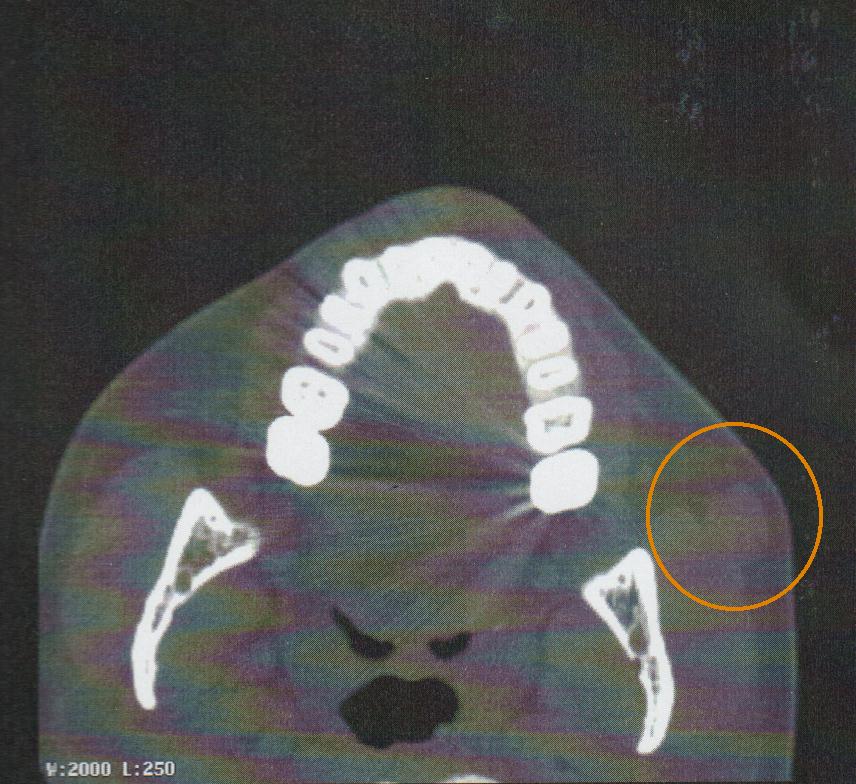

Myoepithelioma is a benign tumor of the salivary gland that mainly affects the parotid gland. The presence of an accessory parotid gland is an anatomical variation and neoplasms in this structure are extremely rare. This paper describes a case of a myoepithelioma arising in the accessory parotid gland of a 29-year-old woman. To the author´s knowledge this is the seventh case reported in English. The patient´s complaint was about a five year growing mass in the left cheek with a sudden growth outbreak. The patient underwent surgery via an intra-oral approach and the histopathology and the immunohistochemistry disclosed a myoepithelioma.